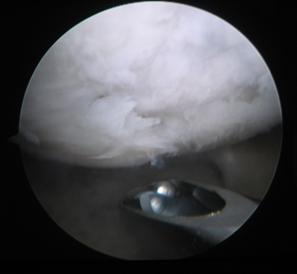

1.3. Diagnosticul Artroscopic al leziunilor cartilajului articular

Examinarea artroscopica a genunchiului ramine standardul de aur in diagnosticarea si evaluarea leziunilor cartilajului articular. Examenul artroscopic permite evaluarea suprafetei cartilajului, a rezistentei la presiune, dar mai ales a marimii si profunzimii zonei leziunii condrale. Numeroase sisteme de clasificare a leziunilor cartilajului articular au la baza examinarea artroscopica directa a acestuia (vezi capitolul 2).

Examinarea artroscopica a cartilajului permite evaluarea mai multor caracteristici ale acestuia. Rezistenta cartilajului la presiune se efectueaza cu ajutorul exploratorului (probe), si se refera la forta cu care acesta este impins inapoi dupa ce presiune a incetat. Persistenta unei depresiuni condrale este semn de "inmuiere" a cartilajului. Artroscopic se evalueaza si culoarea cartilajului care normal este alba, lucioasa, cu usoara tenta galbuie. Cartilajul artrozic are o culoare galbuie marcata, este mat.

La examinarea artroscopica suprafata cartilajului este neteda, lucioasa, o fara discontinuitati. Pierderea luciului, prezenta unor depresiuni, fisuri, fibrilatii, delaminari sint semne de leziune. De asemenea, o zona de ingrosare a cartilajului, depresibila la examinarea cu exploratorul, este semnul unei leziuni profunde: "blister".

Modificari ale formei si conturului suprafetelor articulare in fracturi, osteocondrita, precum si prezenta de osteofite marginale in artroza (fig. 1.12) pot fi observate in cursul examinarii artroscopice a genunchiului.

Fig. 1.13. Imagini artroscopice - leziuni osteocondrale stadiu III B si C ICRS la nivelul condilului femural si la nivelul patelei |